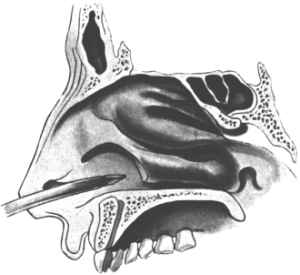

| 345. | Catheterizing the Sphenoidal Sinus | 654 |